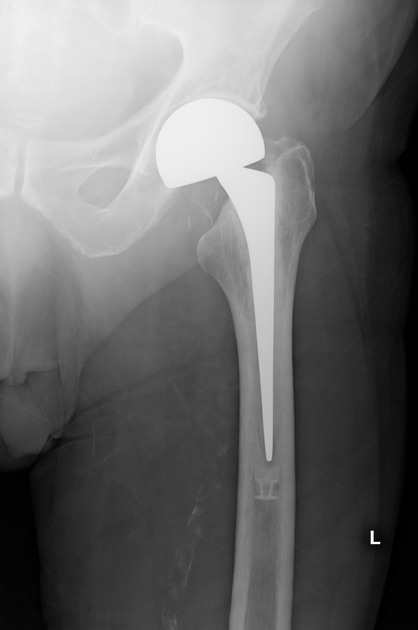

Example 4

Diagnosis

Hemiarthroplasty

Image 4: Hacking, C., El-Feky, M. Hip hemiarthroplasty. Reference article, Radiopaedia.org. https://doi.org/10.53347/rID-37709